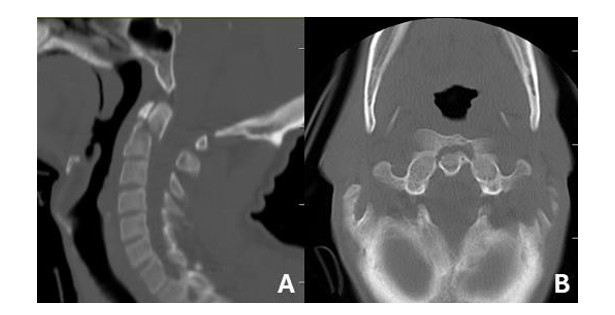

A 39-year-old male presented to the emergency department after sustaining a 4-meter fall from a roof on June 3, 2013. On arrival, the patient was conscious with a Glasgow Coma Score of 15 and exhibited no neurological deficits. Cervical and thoracic imaging revealed a posteriorly displaced Type II odontoid fracture (Anderson and D'Alonzo classification) and a T5 rotational burst fracture-dislocation [4]. Cervical CT imaging confirmed posterior displacement of the odontoid (see Figure 1), while thoracic CT imaging revealed a T5 rotational burst fracture with minimal canal encroachment. (see Figures 2 and 3). No additional fractures were identified.

Figure 1: (A) sagittal and (B) axial CT showing a posteriorly displaced Type II odontoid fracture